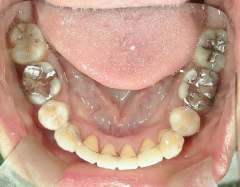

矯正歯科 治療前